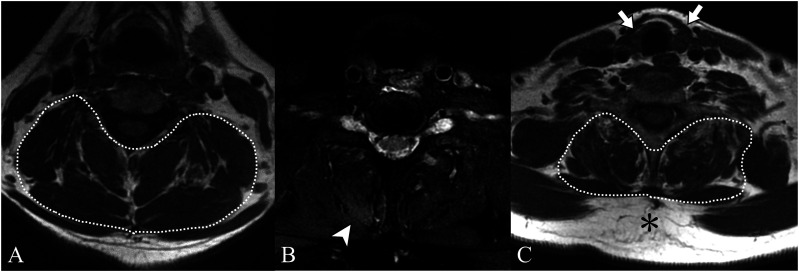

Dropped head syndrome, characterized by excessive flexion of the neck, frequently leads to significant impairment in quality of life. Among the various causes of this syndrome, some cases respond effectively to internal medicine. We report a case of a woman in her 70s who presented with dropped head syndrome and was finally diagnosed with hypothyroid myopathy limited to the extensor muscles of the neck. Cervical spine MRI at the initial examination indicated thyroid atrophy, increased subcutaneous fat, and a mild high signal in the right cervical extensor muscles on fat-suppressed T2-weighted images. Blood tests confirmed hypothyroidism. Treatment with levothyroxine improved the symptoms and normalized the blood test results. This case highlights the importance of careful evaluation of the thyroid gland and paravertebral muscles in cervical spine MRI. They can offer diagnostic clues for underlying the important causative role of thyroid disease in dropped head syndrome.